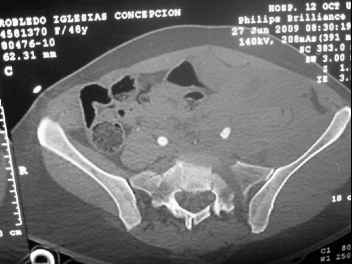

41 yo female , fall from 10 meters five days ago. Hemodynamically unstable on admission treated by angio and embolization and skeletal traction, with no external support. No associated injuries.

Based on CT scan the pt has a both column fracture with conminuted dome and displaced anterior column and a sacral Denis 1 fracture with a displaced left ala. I think the best approach for the acetabular fracture is ilioinguinal with Smith-Petersen extension but don't know exactly the sequence . Will you start with the sacral fracture? Which technique?